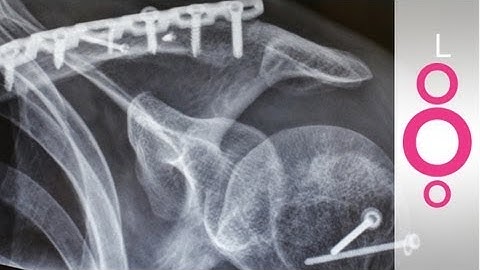

Chinese Scientists Create 'Bone Glue' To Fix Fractures In Just 3 Minutes | Anchor Nirupama